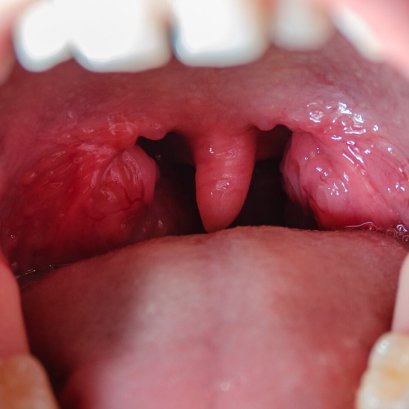

การผ่าตัดทอนซิล อะดีนอยด์ รักษานอนกรน

การผ่าตัดตกแต่งลิ้นไก่เพดานอ่อนและคอหอย รักษานอนกรน